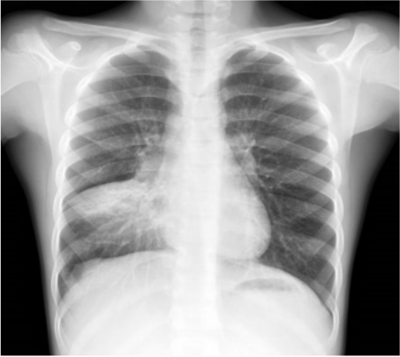

Adolescente masculino, 13 anos de idade, portador de anemia falciforme em seguimento regular com hematologista, apresenta queixa de febre e tosse há dois dias e dor em face anterior do tórax a direita. Ao exame clínico encontra-se em regular estado geral, levemente descorado, FC: 84 bpm, FR: 34 ipm, Saturação de Oxigênio: 95% em ar ambiente, Temp: 38°C, PA: 100/60 mmHg. Realizou radiografia de tórax, que mostrou a imagem abaixo:

A conduta inicial mais adequada é: